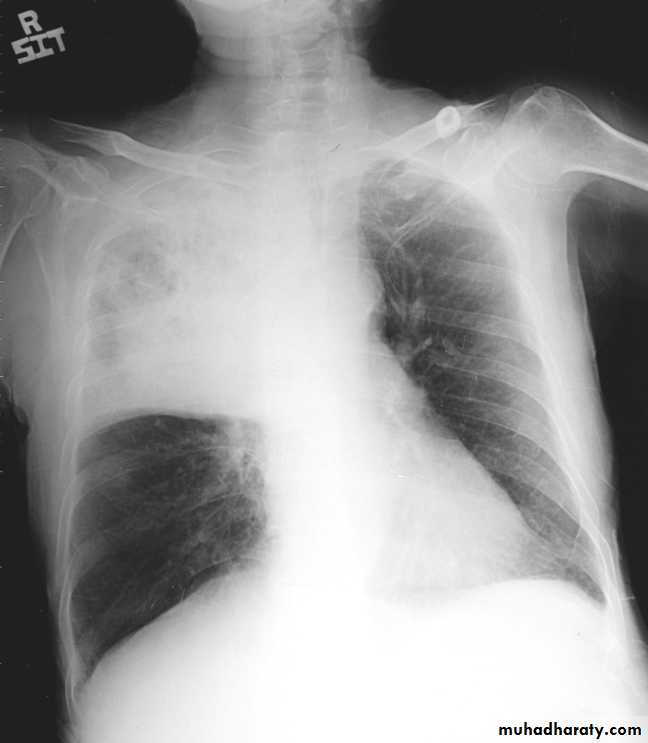

Pleural effusion

50.pleural effusion

51.pleural effusion .